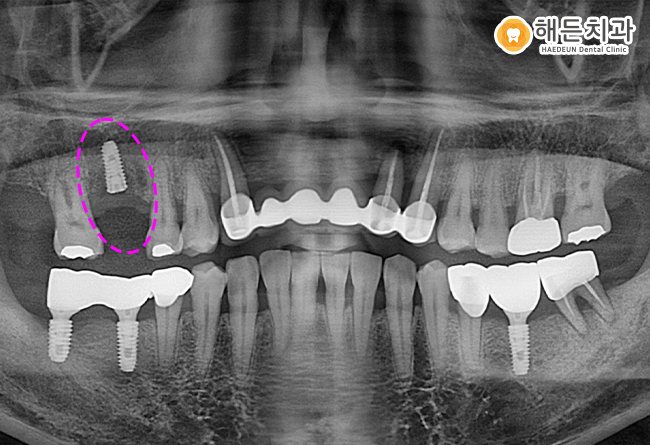

위 사진은 해든치과에 내원하신 노*석님의 치아 사진입니다.

위의 환자분께서는 오른쪽 위아래 어금니가

불편하고 통증이 있다며 본원을 찾아주셨습니다.

정밀검진을 위해 파노라마 사진을 촬영하여 확인해보니,

환자분이 불편감을 느끼는 부위는 상태가 너무 좋지 않았습니다.

오른쪽 위의 맨 후방에 위치하고 있는 사랑니는 충치 진행이 너무 심하여 발치가 필요한 상태였습니다.